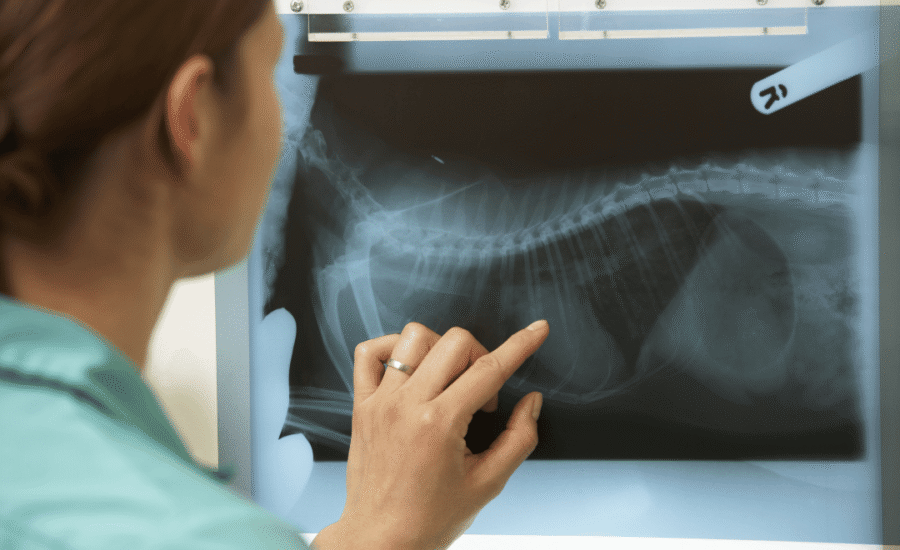

De diergeneeskunde staat aan de vooravond van een digitale revolutie. Slimme diagnostiek bij dieren: van röntgen tot MRI is volop in ontwikkeling dankzij AI-technologie. Waar dierenartsen nu nog vooral vertrouwen op hun getrainde oog, kan kunstmatige intelligentie